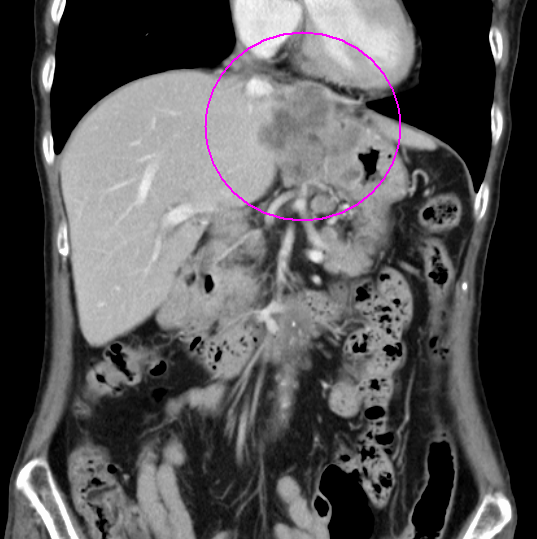

術前化学療法の例(造影CT画像)

治療前

治療後